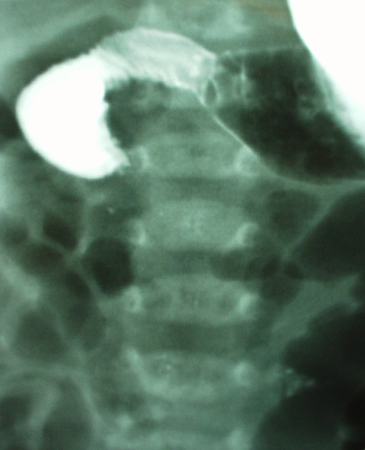

Upper GI contrast study demonstrating malrotation with volvulus. The duodenum fails to develop the normal anatomical C-loop. There is failure of contrast to pass, resulting in a characteristic bird beak consistent with acute mid-gut volvulus

From the collection of Dr KuoJen Tsao; used with permission